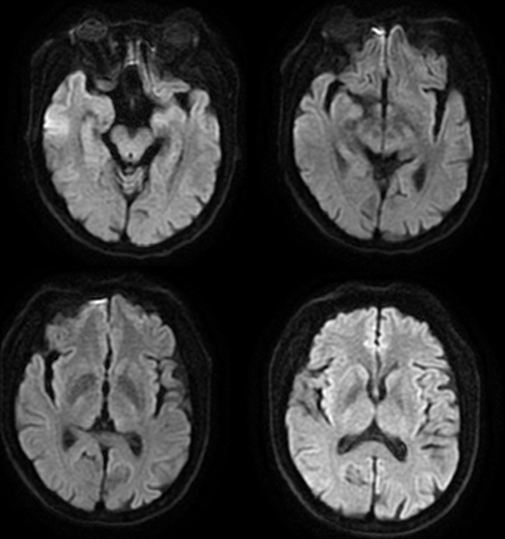

DWI

MRI 影像描述:T1W1 可见双侧苍白球对称高信号,T2、T2FLAIR、DWI 相应部位均未见确切异常信号。

普遍接受的 HE 颅脑 MR 常规成像特点为 T1WI 上基底节区尤其是苍白球双侧对称性高信号,其他部位如黑质、中脑被盖以及垂体等也可出现异常高信号;T2WI 上多无明显改变,组织学证实苍白球密度增高是猛沉积的结果。健康人在摄入锰之后可迅速被肝脏清除,并排出人胆道系统。肝硬化病人锰经胆道排泄减慢,导致血锰水平升高及脑中锰聚集增加。因锰离子在第 3 轨道有 5 个不配对电子而具有较大磁矩,能明显缩短 T1 弛豫时间,导致 T1WI 高信号。